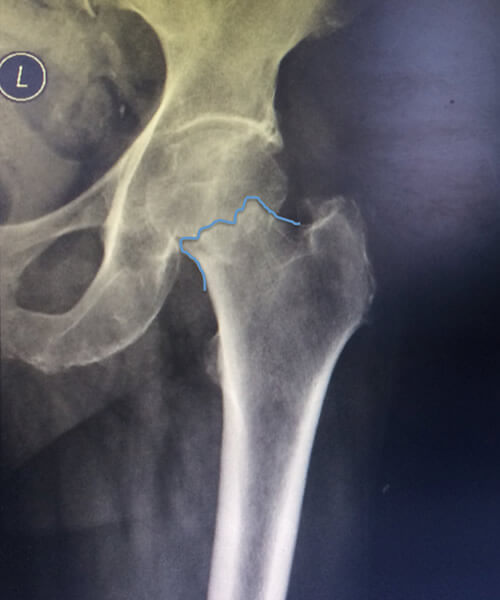

1 Fratura do Colo do Fêmur 2 Fratura do Colo do Fêmur

Fig. 1 e 2 - Fraturas do Colo do Fêmur